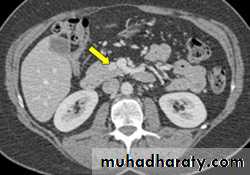

Acute Pancreatitis

CT used to

• 1. Pancreatic necrosis .• 2. An abscess.

• 3. Vascular complications.

• 4. Pseudocyst

1

3

2

4